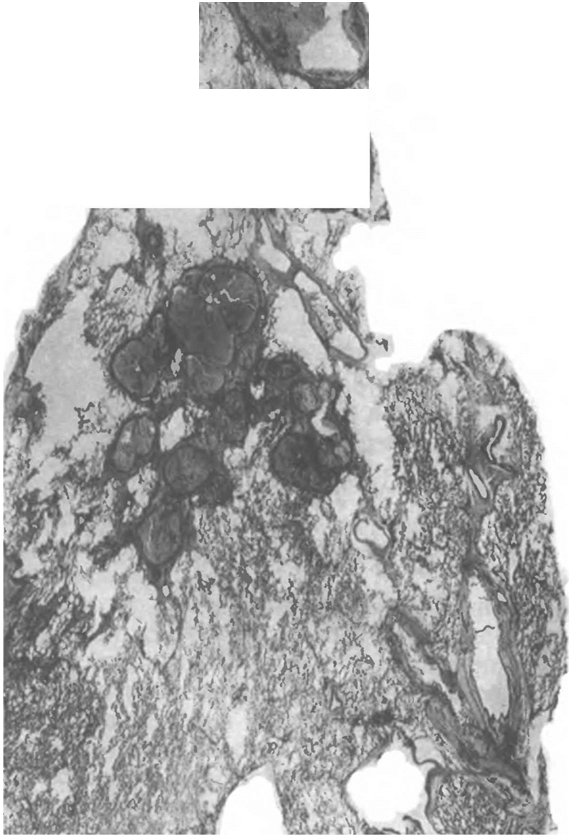

Рис 19 Кавернозный ту беркулез

Гистотопограмма Окраска ге-

матоксилином и эозином

исходить по типу очищения внутренней поверхности каверны и перехода ее в кистоподобную полость (рис. 1.9).

Фиброзно-кавернозный туберкулез характеризуется наличием в одном или в обоих легких каверны или каверн, расположенных среди фиброзно измененной легочной ткани. В стенках каверн в отличие от кавернозного туберкулеза фиброзный слой, как правило, резко выражен и превалирует над казеозно-некротическим и грануляционным (рис. 1.10). Вблизи каверн обычно имеются очаги бронхогенной диссеминации, инкапсулированные или свежие.